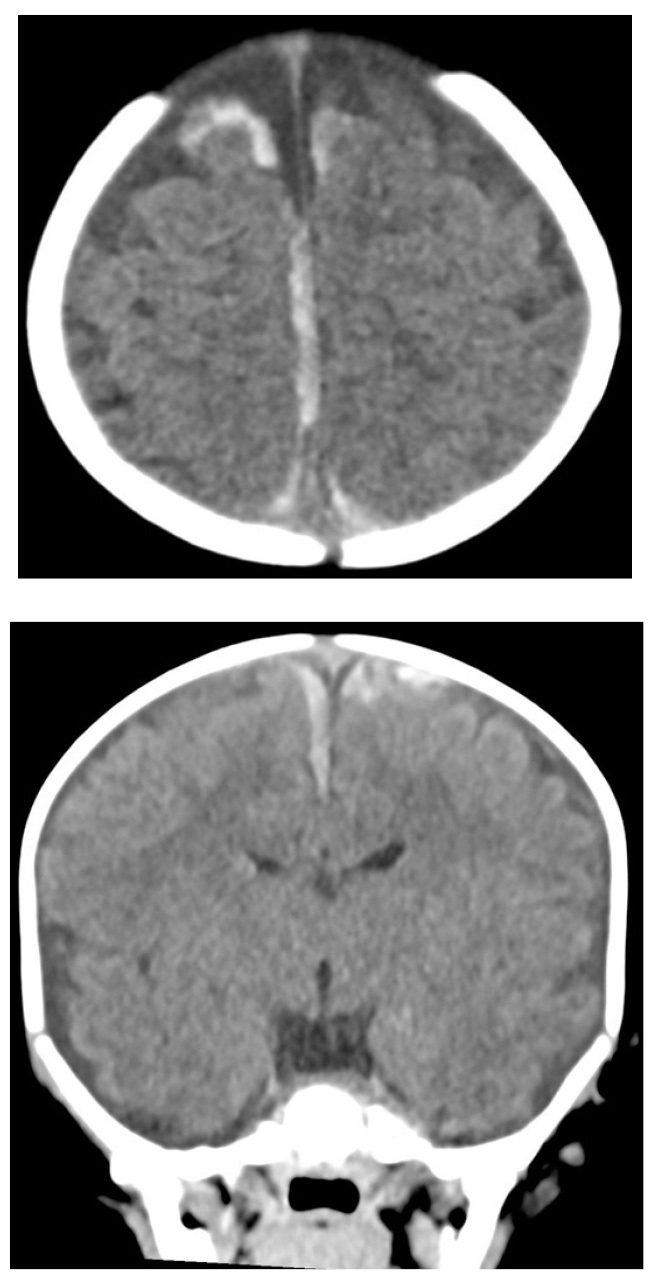

Children who are being evaluated for nonaccidental trauma (NAT) typically undergo skeletal survey X-rays and CT scans of the head. Skeletal surveys require interpretation by an experienced radiologist. If the suspicion is significant, a chest CT may be warranted for an improved assessment of rib fractures. Typically, a skeletal survey is completed initially, which consists of plain films. If this is negative, a follow-up skeletal survey often is repeated in several weeks, since injuries may be more readily apparent on imaging at that time. Low-dose CT scan of the chest may detect rib fractures more accurately and quickly. This could lead to faster diagnosis and reduced need for coordinating repeat imaging.55 It has been noted that 17% of rib fractures were not identified by X-rays. CT scans were more sensitive in recognition of rib fractures when performed within a month of each other. Acute injuries without significant calcification especially were better identified on CT scans.55 Across all radiologists, three times as many rib fractures were correctly detected by using chest CTs compared with chest radiography.56 Patients in whom there are concerns for possible child abuse deserve special consideration. When there is suspicion for NAT in infants, CT scan of the head should be performed even in the absence of obvious external injuries to the face or scalp or definitive head trauma. For an example of abusive head trauma, see Figure 9.

Figure 9. Extra-Axial Hemorrhages |

![]() |

Axial and coronal images from noncontrast head computed tomography show bilateral paramedian extra-axial hemorrhages, typical of bridging vein injury from abusive head trauma. Source: Courtesy of Mark Warren, DO, Dayton Children’s Hospital, Department of Radiology |